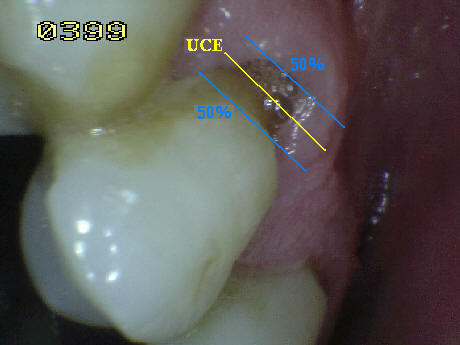

Consideraciones

- Cuando la superficie de la corona y la raíz estén afectada

por caries deben ser identificadas independientemente.

En caso de duda porque la lesión de caries se encuentra en la

unión cemento-esmalte (UCE) debe analizarse que superficie

esta más afectada o que se extienda por lo

menos 1 mm o más allá del limite de la unión cemento esmalte (UCE),

en ambas direcciones cervico-incisal y cervical apical, debe

considerase cual es la más extensa aplicando la regla del

50% , si existe igualdad el examinador debe decidir si la lesión

es codificada como de raíz o de corona, o en su defecto puede

aplicar ambas. Ver imagen derecha.